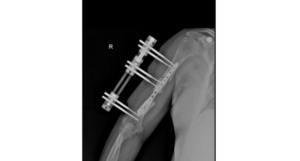

Methods of Bone Transport for Humeral Defect Reconstruction

The Hoffmann Fixator, a widely recognized external fixation device in orthopedic surgery, has been instrumental in the treatment of fractures and complex limb injuries. This